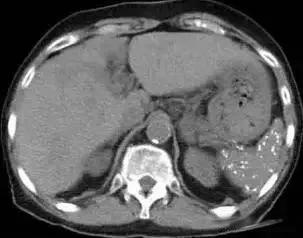

脾脏钙化是指在脾脏内出现类似结石一样的强回声或高密度影像的钙质沉淀。 这种现象在体检中并不罕见,但很多人对其原因和临床意义并不了解。事实上,脾脏钙化可能由多种因素引起,其中最常见的包括感染、外伤、肿瘤等。

值得注意的是, 脾脏钙化本身通常没有临床症状,也不会对身体产生明显影响。 然而,它可能是某些潜在疾病的表现,因此需要引起重视。通过影像学检查,如B超和CT,医生可以初步判断钙化的原因。例如,结核引起的钙化可能表现为弥漫性钙化点,而肿瘤则可能有其特征性的影像学表现。